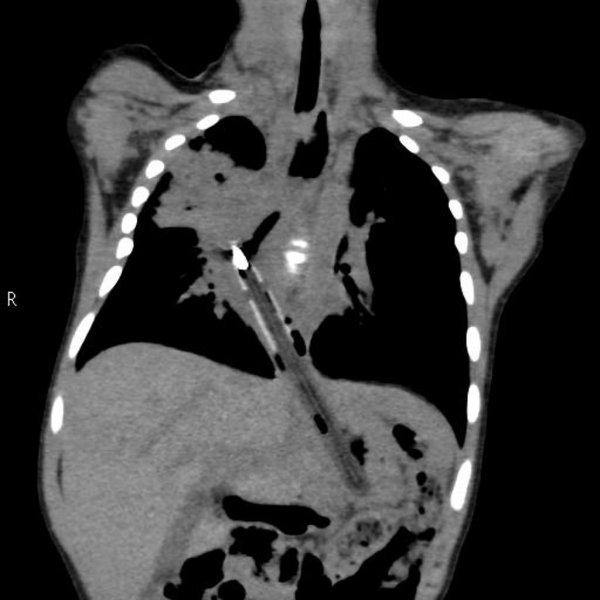

Специалисты по рентгеновской диагностике регулярно сталкиваются с посторонними предметами внутри тела человека. Обычно лишние предметы попадают в пищеварительную систему из-за неосторожности при еде или во время неудачных любовных игр. Почти всё удается вытащить — с хирургическим вмешательством или без него. выбрал самые необычные находки радиологов, которыми они делились на сайте Radiopaedia.org.